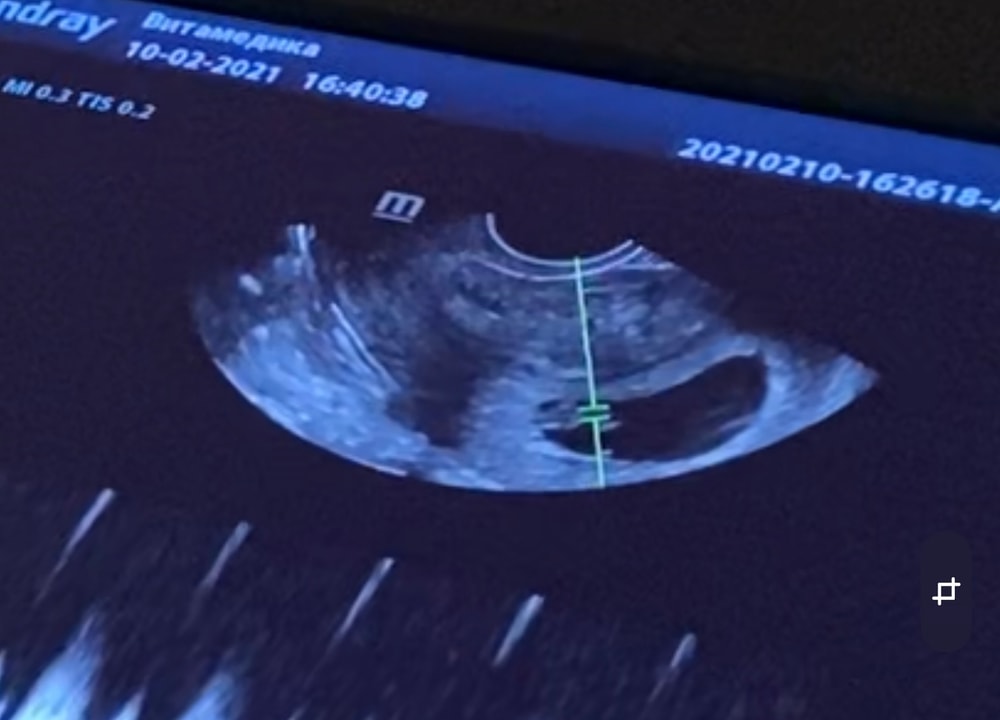

Диана, трансвагинсльно ,но в интернете нашла такую информацию ,то есть у меня по сути Хорион,как у девочки сверху Изображение

Диана, но мне самой больше кажется ,что сын ,хотя я за две беременности ни разу не угадала 😂

Леся Леся, я отправляла как то им на сайт ) так вот они мне хорион выделили слева(справа на фото ) ,так как подумали что узи было вагинально ,а узи было через живот и доктор сказал что не зеркалит )) ну посмотрим ,хотя очень много ошибок было по этому методу ))) тут мне кажется не угадаешь ))